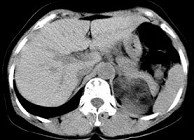

- 单项选择题男性,28岁, 左腰背酸胀5个月,CT检查如图所示, 应诊断为 ( )

A、左肾上腺髓样脂肪瘤

B、左肾上腺错构瘤

C、左肾上腺嗜铬细胞瘤

D、左肾上腺腺瘤

E、左肾上腺转移瘤